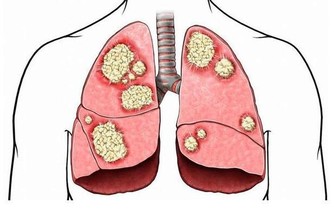

有沒有可能是身體方面的原因呢?自然是可能的。畢竟尿液是經過過濾形成的,尿液來得過快自然不能排除是這方面的因素。不過,一般不會是單純地喝水後就想尿,還會伴隨著其他方面的問題,諸如夜尿次數增多、尿液渾濁之等等。

喝水多沒有尿意,一般認為是少尿或者是無尿的情況。無論是哪一種情況,都和是否喝水,喝水多少並沒有關係,主要是看尿液總量。每天的尿液總量,不到400毫升屬於少尿,不到100毫升屬於無尿。這些情況的出現,和飲水量以及出汗量有關係,飲水少、出汗多的人往往會出現少量的情況,在一些熱衷於運動的人身上比較常見。除去這種生理性因素之外,一樣可能是身體方面的問題。當它的過濾能力逐漸下降時,尿液的形成過程也就出現了問題,尿液量會顯著減少,同樣是不容忽視的。